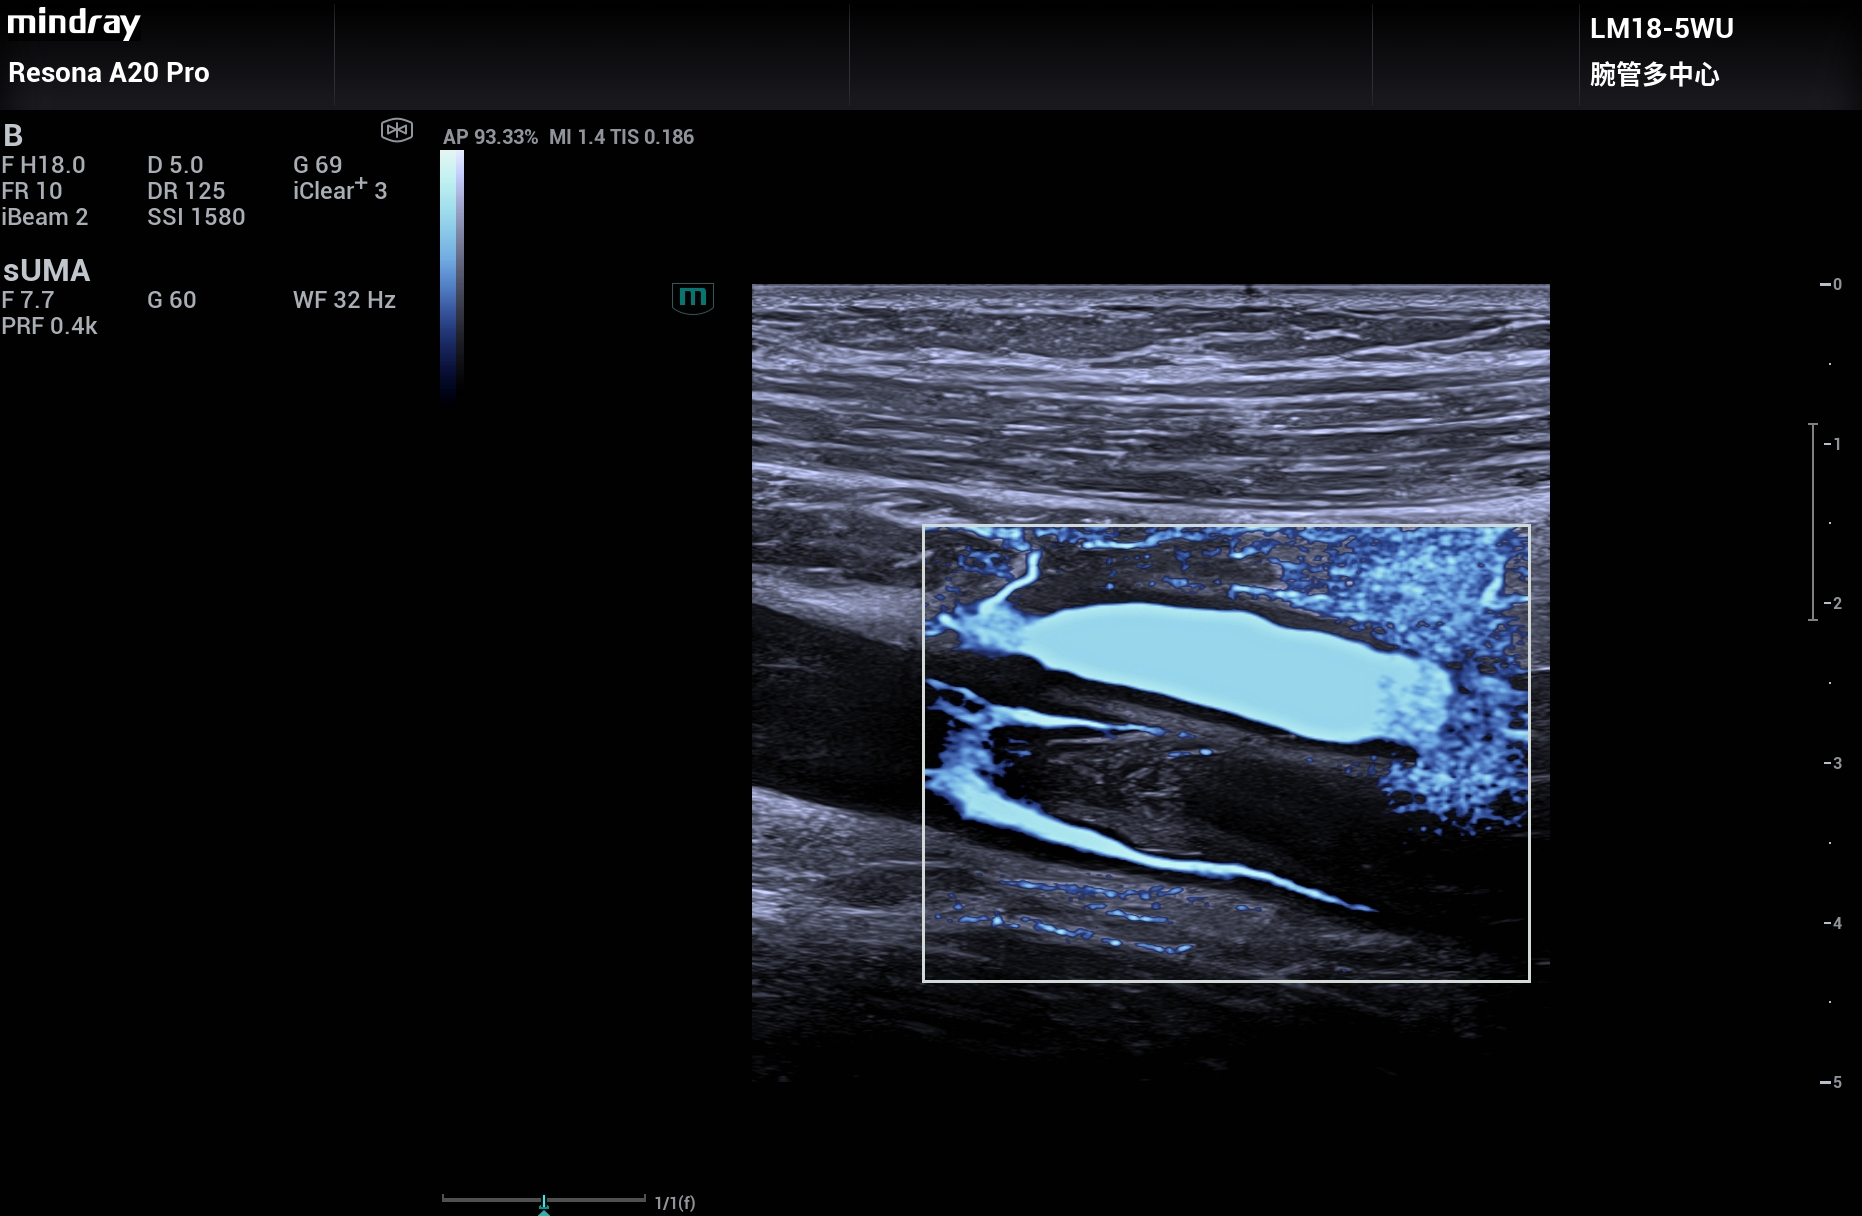

下肢深静脉血栓,超微血流能显示血栓内的微小血流,大大提高确诊的信心,Resona A20。